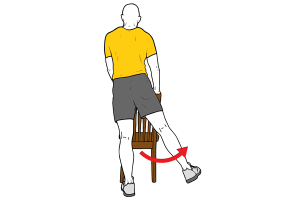

La parte objetiva de la exploración, se realiza primero con el paciente con el zapato, en apoyo monopodal y pidiéndole que se ponga de puntillas. Si el dolor aumenta es un posible signo de neuroma de Morton. También podemos realizar un test de compresión nerviosa, denominado test de Mulder, que consiste en comprimir la cabeza de los metatarsianos a la vez que realizamos una presión sobre el punto doloroso entre ambos dedos de los pies. El test es positivo si al realizar a presión aumenta el dolor y se irradia hacia los dedos de los pies.

Otras de las pruebas que podemos realizar es comprobar si a la flexión dorsal del tercer dedo del pie, aparece el dolor. Y la prueba de distracción que solemos utilizar es una separación de los metas donde la persona nos diga que siente más dolor.